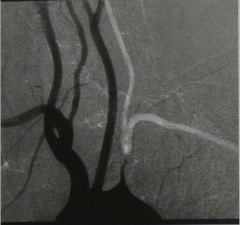

1. Имплантация ПкА в общую сонную артерию (рис. 1). Эта операция восстанавливает прямой кровоток по ПкА и не требует применения шунтирующего материала. Гемодинамическая эффективность операции не оспаривается: ликвидируя СППО и восстанавливая прямой кровоток по ПкА, она компенсирует наступающее обкрадывание бассейна общей сонной артерии (не более 10 – 15% от каротидного кровотока) и увеличивает суммарный кровоток по общей сонной артерии и ПА приблизительно в 1,5 раза от исходного.

2. Сонно-подключичное шунтирование (рис. 2). Эта операция выполняется при распространении стеноза на 2-й сегмент ПкА, а также у больных гиперстенического телосложения, когда выделение 1-го сегмента ПкА сопряжено с техническими трудностями. Преимуществом данной операции является техническая простота ее выполнения. К недостаткам можно отнести отсутствие прямого кровотока в ПкА и необходимость использования пластического материала.

3. Подключично-подключичное перекрестное шунтирование (рис. 3). Этот вид реконструкции выполняется при наличии поражения ипсилатеральной общей сонной артерии.